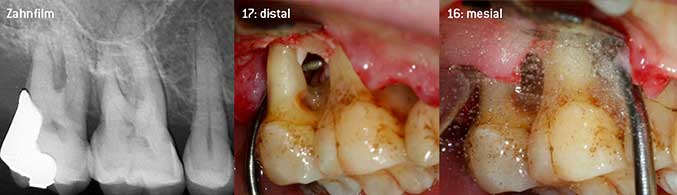

Als Initiatoren zur Entwicklung der neuen diamantierten Luftscaler-Spitze 3AP sahen es beide Zahnärzte als notwendig an, die Einschränkung in der Handhabung bisher kommerziell vermarkteter diamantierter Spitzen insbesondere während der Furkationstherapie oder in engen Knochentaschen zu verbessern. Dies sollte unabhängig von nicht-chirurgischem (Abbildung 2) oder chirurgischem Vorgehen sein (Abbildung 3).

(Fotos Abb 2 -4: © Dr. Chr. Graetz)